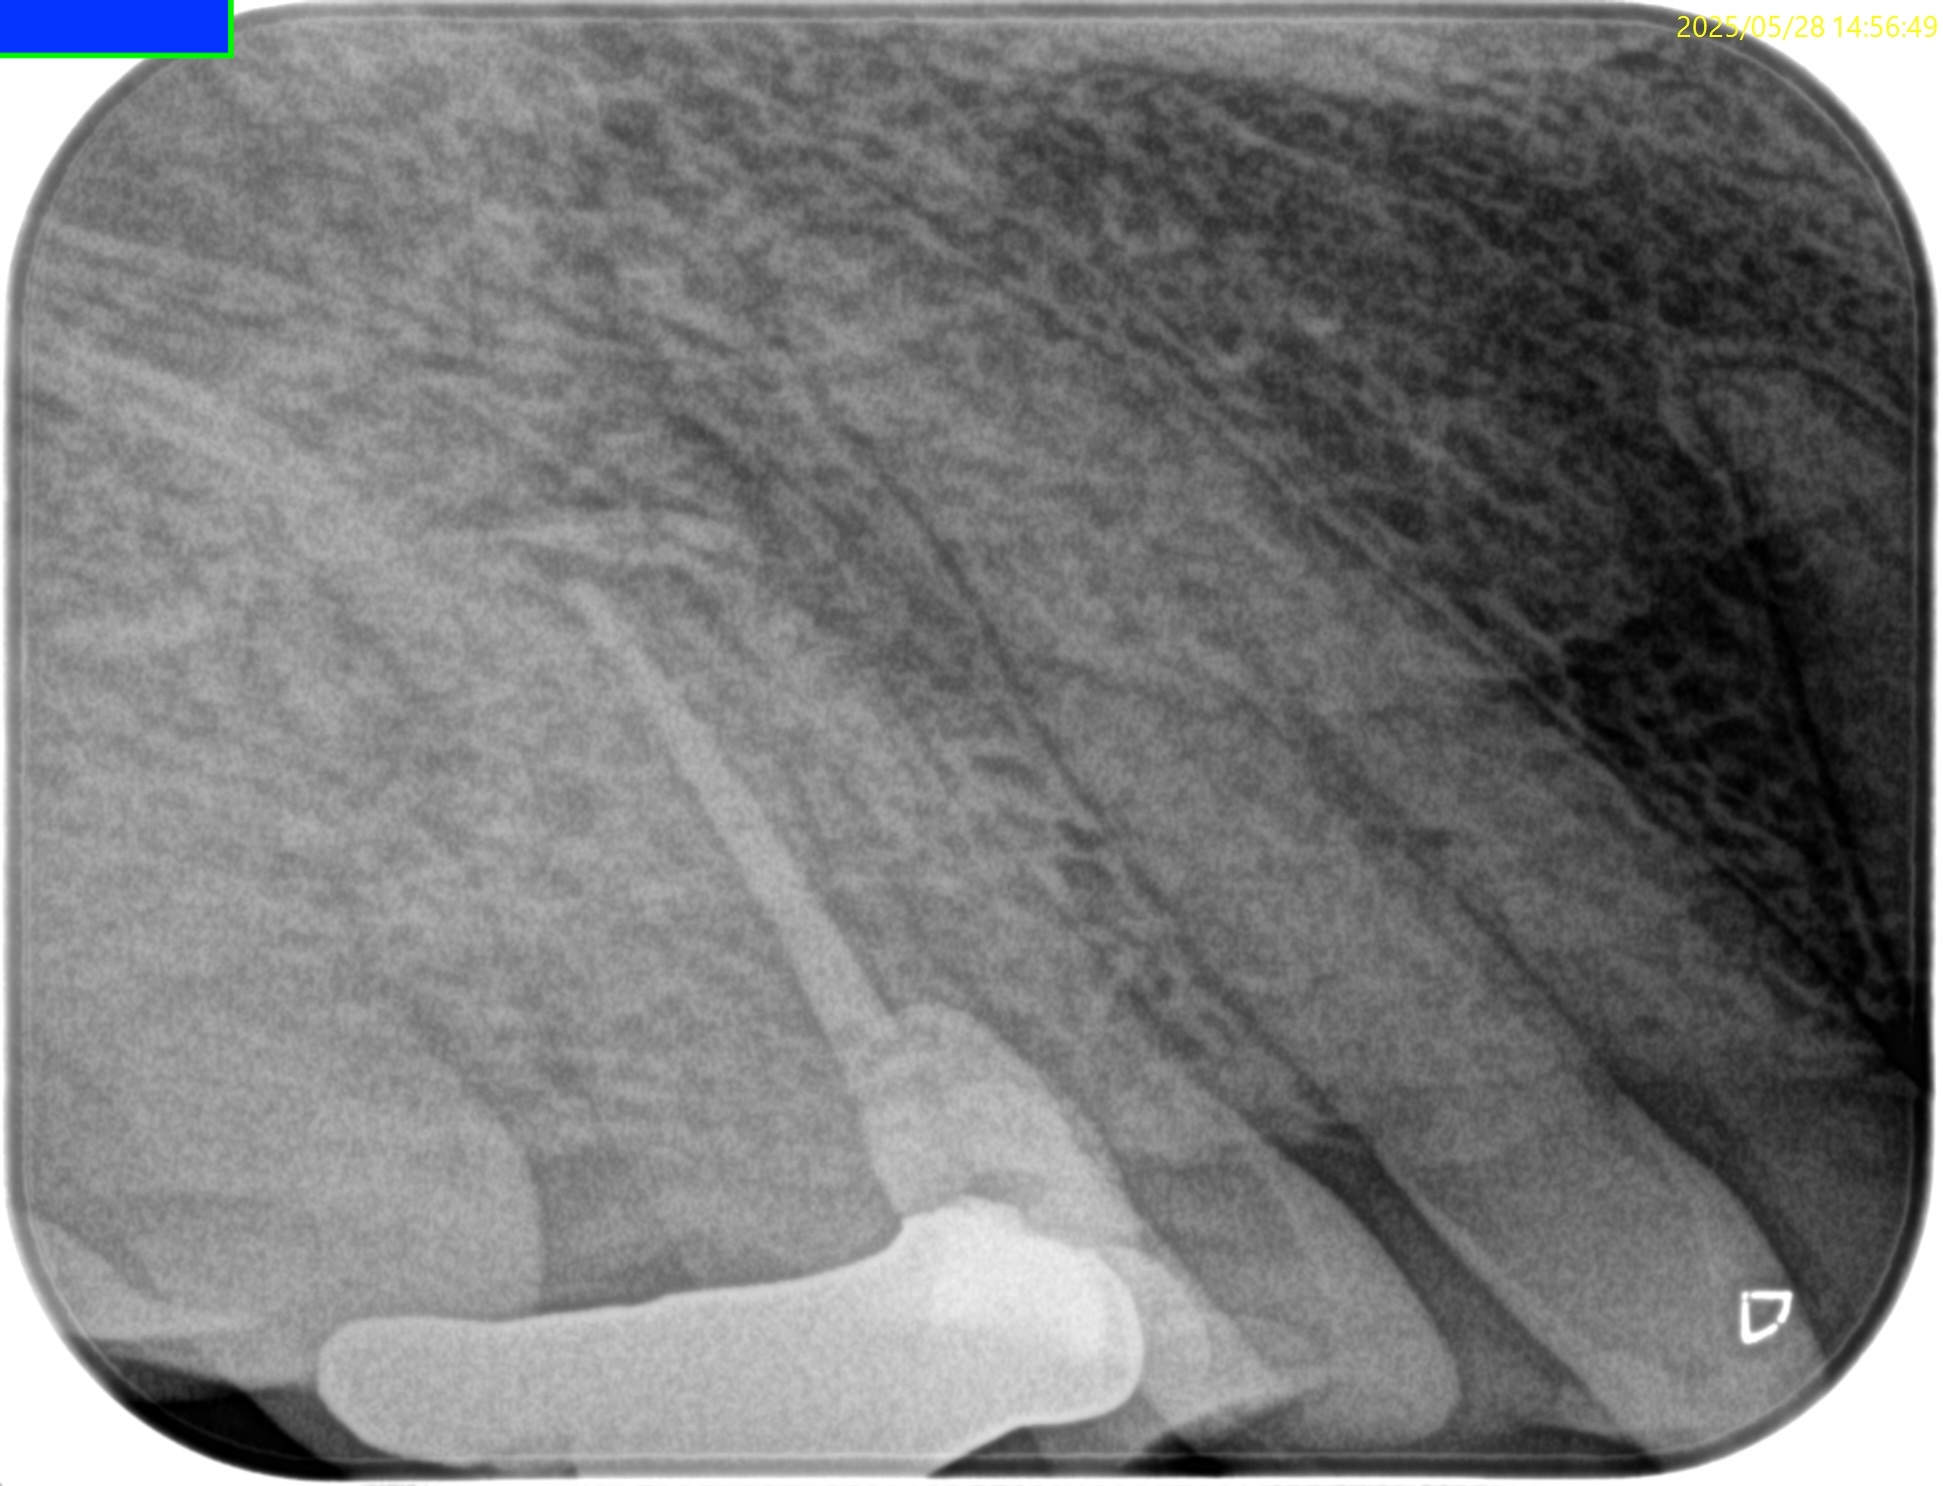

#4 RCT(2025.5.28)

生活歯髄療法で根管が石灰化していたため、#17の短針でスカウティングしている。

C+ File #10→8→6→K File #10→#8で根管が穿通した。

したがって、K Fileを1mm突き出した。

PA,CBCTを術後に撮影した。